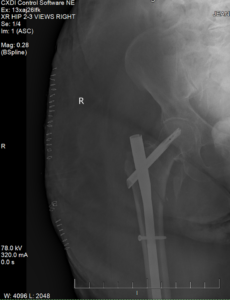

EMS rushed our client to the emergency room at St. Mary’s Hospital. Doctors ordered X-rays, which showed a major fracture of her femur near the hip, and an MRI of her neck showed a severe spinal cord compression:

She underwent multiple major procedures, including:

- Surgical repair of the femur with an intramedullary rod and screws